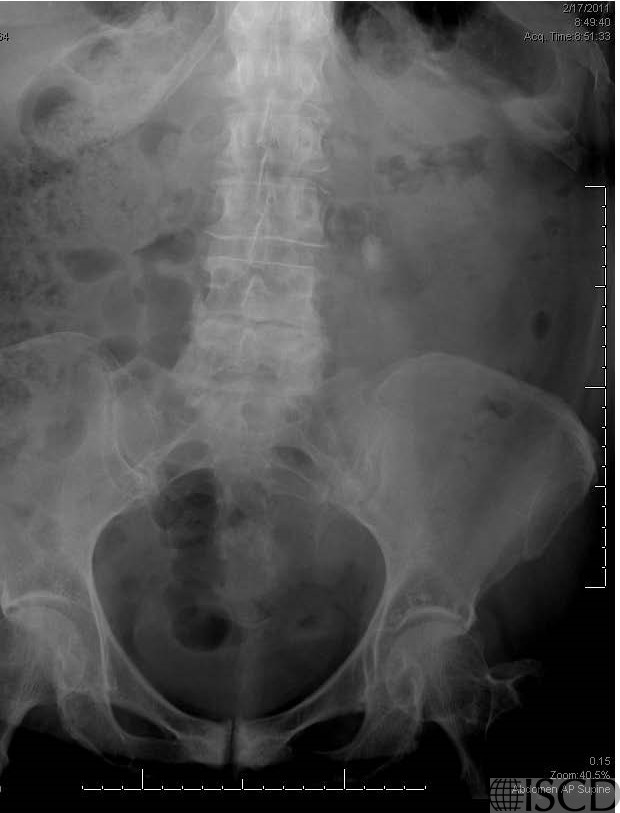

There is an opacity lateral to L2 on the left that was proven to be a kidney stones.

The accompanying supine abdominal film demonstrates the left kidney stone in the renal pelvis.

There is a renal stone lateral to L2 on the spine DXA. The corresponding radiograph shows a 1.5 x 1 cm calcification overlying the medial left renal outline. It was read as being consistent with a stone within the renal pelvis. On the Hologic “undo” view, the stone was removed from the soft tissue baseline. Individuals with kidney stones have been show to have lower bone mineral density and higher fracture risk than individuals without kidney stones.